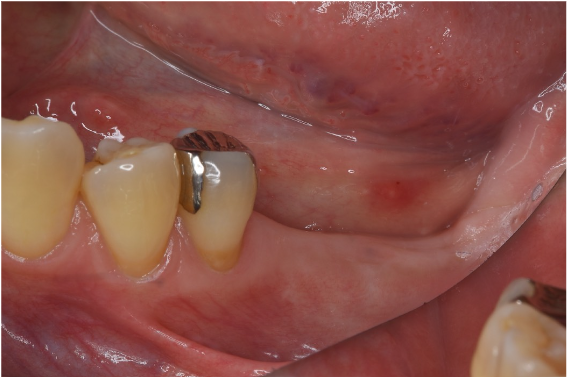

症例3

| 項目 | 詳細 |

|---|---|

| 患者様データ | 50代 男性 |

| 来院時の主訴 | 「左下で噛むと違和感がある。」 |

| 医院の診断 | 左下第二大臼歯の歯根破折 |

| 通院期間 | 9か月 |

| 来院回数 | 12回 |

| 治療費 | 総額:835,000円(税抜) 【内訳】 インプラント埋入手術250,000円、GBR(骨再生手術)150,000円、2次手術+FGG(遊離歯肉移植術)55,000+60,000円、仮歯30,000円、インプラント上部構造(セラミッククラウン)170,000円、隣在歯セラミッククラウンのやりかえ120,000円 |

| リスクと副作用 | 定期的なメンテナンスが必要、術後若干の腫れと痛み |

| ここがこだわりのポイント!☝ | インプラント周囲に角化歯肉と言われる健常な歯肉がなかったので、口蓋からの歯肉移植を行っています💡この角化歯肉がないと、インプラントをしてもうまく歯磨きができないことがあります。 |